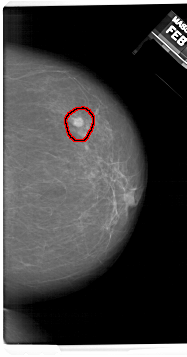

A_1409_1.RIGHT_MLO

RIGHT_MLO LINES 6451 PIXELS_PER_LINE 3736 BITS_PER_PIXEL 12 RESOLUTION 43.5 OVERLAY

FILE: A_1409_1.RIGHT_MLO.OVERLAY

TOTAL_ABNORMALITIES 1

ABNORMALITY 1

LESION_TYPE MASS SHAPE ROUND MARGINS ILL_DEFINED

ASSESSMENT 4

SUBTLETY 4

PATHOLOGY BENIGN

TOTAL_OUTLINES 1

BOUNDARY